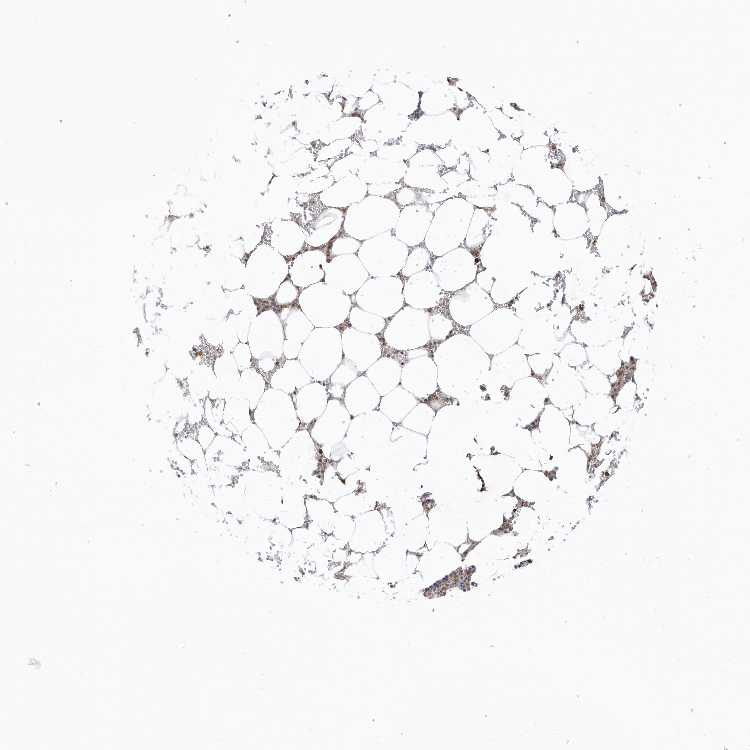

BONE MARROW - Antibody stainingi

Antibody staining in the annotated cell types in the current human tissue is reported as not detected, low, medium, or high, based on conventional immunohistochemistry profiling in selected tissues. This score is based on the combination of the staining intensity and fraction of stained cells.

Each image is clickable and will lead to virtual microscopy that enables deeper exploration of all samples and also displays staining intensity scores, fraction scores and subcellular localization as well as patient and tissue information for each sample.

Antibody HPA035399

Hematopoietic cells Medium